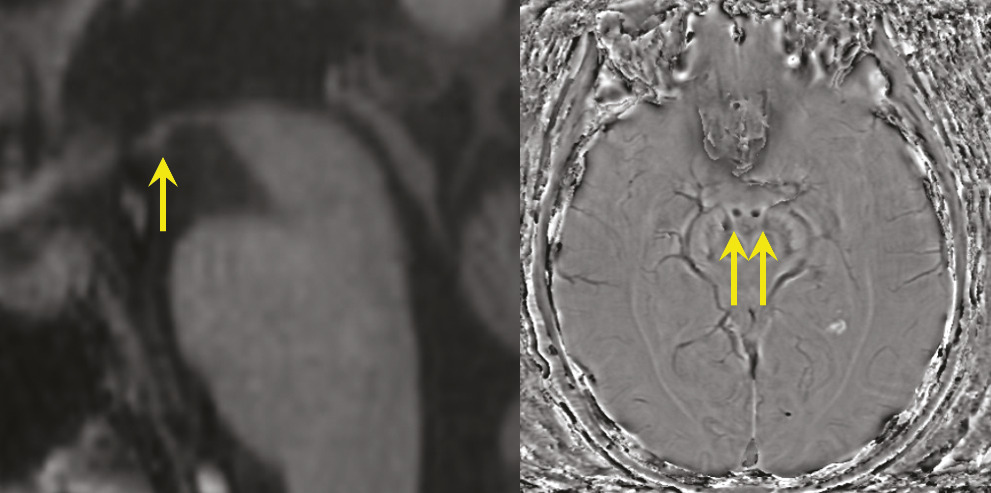

Très récemment ont été décrites des encéphalites toxiques dues à des opioïdes3 ou à des drogues telles que la MDMA (ecstasy), qui lèsent électivement le circuit de Papez (fig. 3 ).

Très récemment ont été décrites des encéphalites toxiques dues à des opioïdes3 ou à des drogues telles que la MDMA (ecstasy), qui lèsent électivement le circuit de Papez (